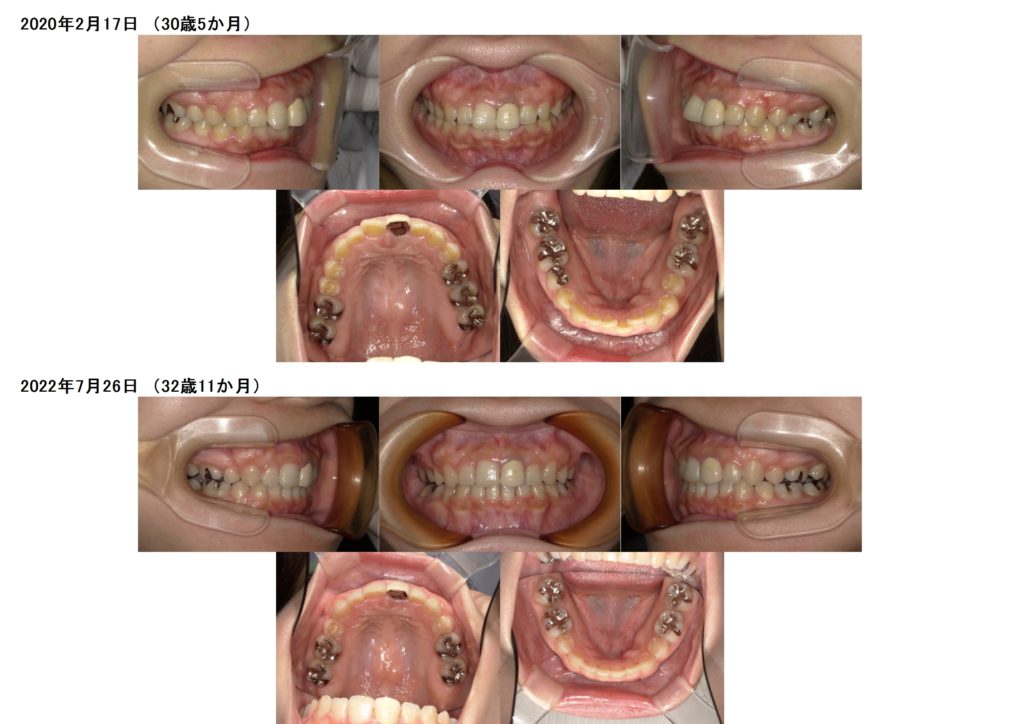

治療前、治療後の口腔内の写真になります。

お口元も随分と変わりましたよっ☆